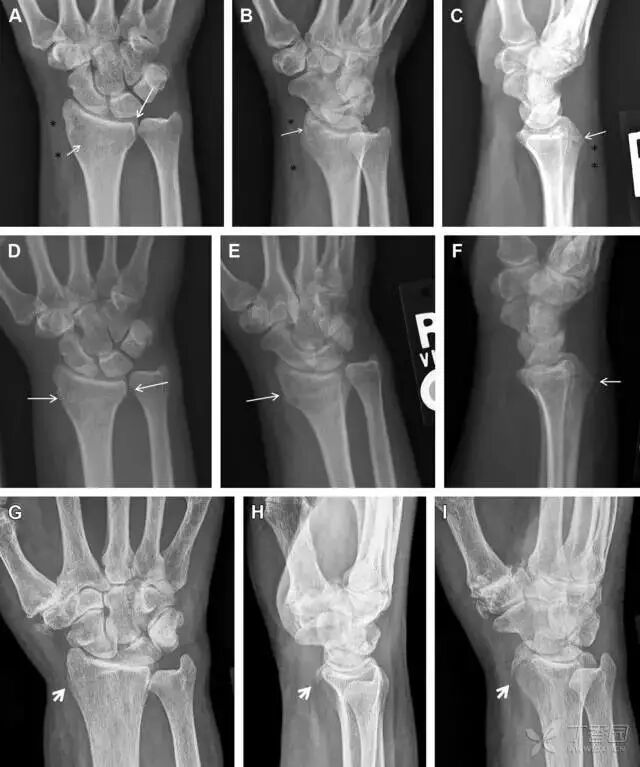

桡骨远端骨折

常规进行前后位、侧位、斜位 X 线检查,对于大多数桡骨远端骨折来说不容易漏诊;但是对于无移位的骨折,特别是桡骨茎突骨折,容易漏诊。桡骨茎突骨折是一斜行的骨折,常累及关节面,常发生于轴向应力或直接打击。

图 1 57 岁女性,摔倒后手掌撑地,桡骨茎突压痛。(A~C)前后位、斜位、侧位片示软组织肿胀(*)和发丝样骨折(白色箭头);(D~F)2 周后,前后位、斜位、侧位片示骨折线显明,由于新骨痂沉积而呈现透亮线与硬化线并存;(G~I)另一患者,桡骨茎突骨折在前后位及侧位片上显示不明显,而在斜位片显示更清楚。

舟状骨骨折

舟状骨骨折 60%~70% 发生于腰部,15% 发生于近极, 10% 发生于远极, 8% 发生于远端关节面。除了常规的前后位、侧位、斜位片外,还需要拍专门的舟状骨位片(腕关节尺偏,以舟状骨为中心的腕关节前后位片),特别是鼻烟壶有压痛时。

图 2 舟状骨骨折 (A、B)第 1 例患者,舟状骨远极关节内骨折(白色箭头),斜位片显示较清楚(B);(C、D)第 2 例患者,舟状骨腰部骨折(虚线箭头),斜位片显示较清楚(D);(E~H)第 3 例患者,舟状骨近极骨折,常规 X 线片均未看到骨折,而在舟状骨位片上才能见到骨折(虚线圆)。